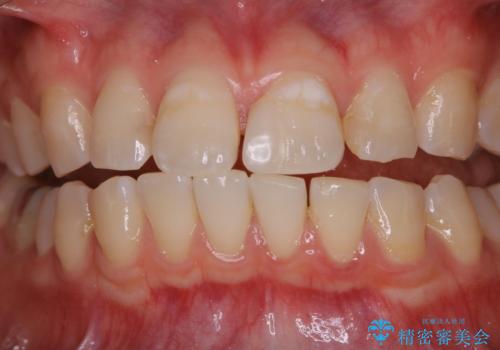

- これからインビザラインでのマウスピース矯正が始まるので、歯石取りをしてほしいとのことでした。

PMTC60分コースを行いました。